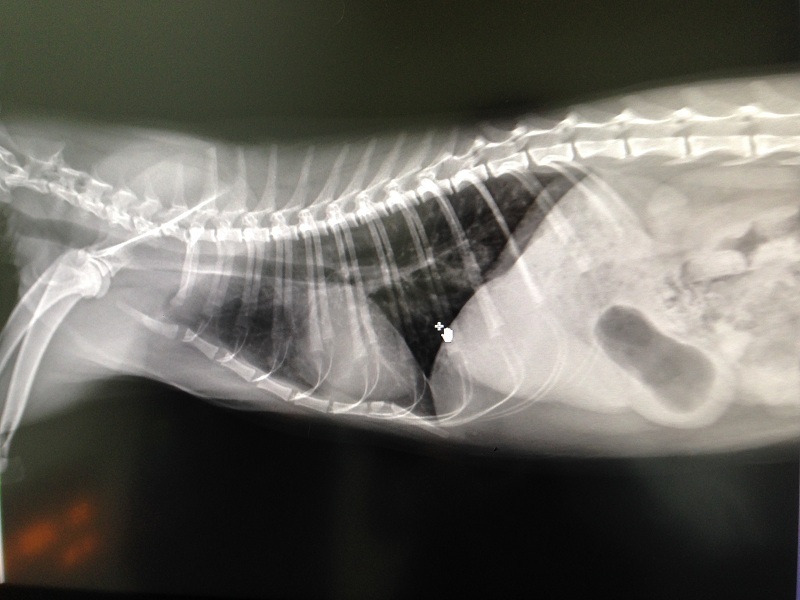

3/21 澄諾回診 喵喵 體重4.62KG

【就診狀況】

回診前幾日喵喵可售的次數變多

所以今日回診時拍攝了不同角度的肺部X光

由X光中看出左肺的白色結點叫右肺多且要來的霧

可算是肺炎的前期,此次的藥物加開類固醇來減緩咳嗽的症狀

但怕肺部中有細菌無法借咳嗽排出體外,故會同時加開抗生素